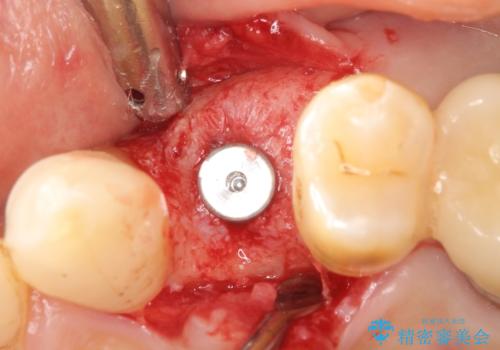

歯科治療や外科手術が苦手な患者様で、治療前はとても怖がっていましたが、インプラント手術後には「思ったよりも大変ではなかった」とおっしゃって下さいました。

元の歯のように咬むことができ、見た目も自然だと喜んで頂けました。

インプラントの種類:スプライン ツイスト

被せ物の種類:メタルボンドクラウン

固定様式:スクリュー固定